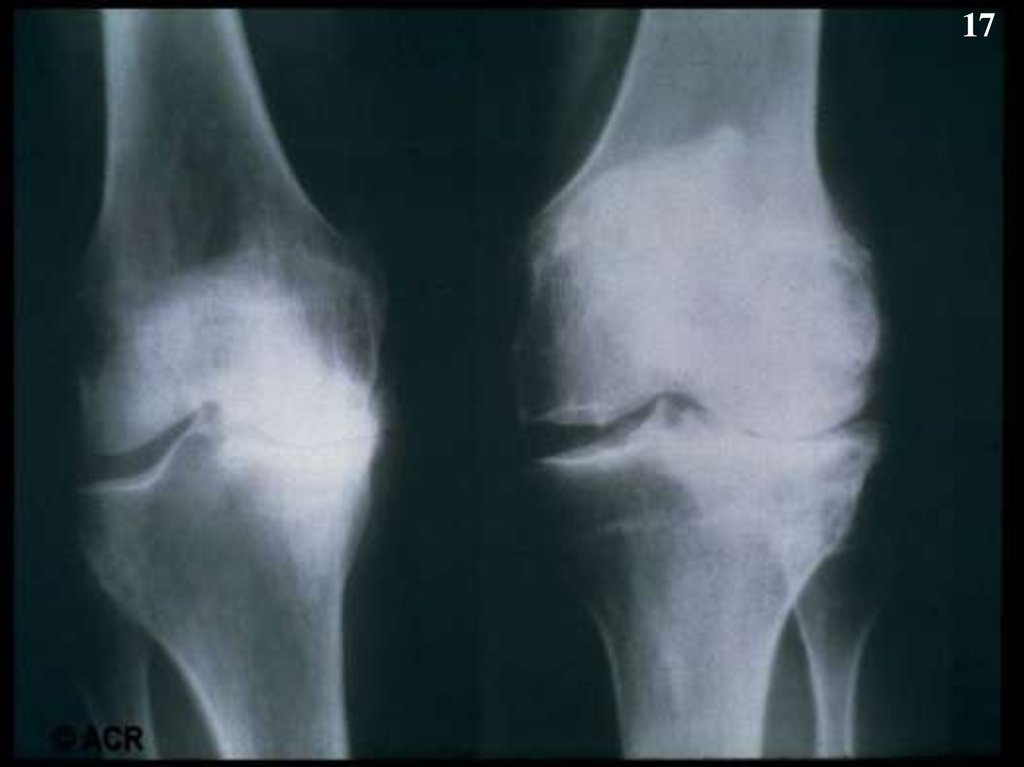

17.

17